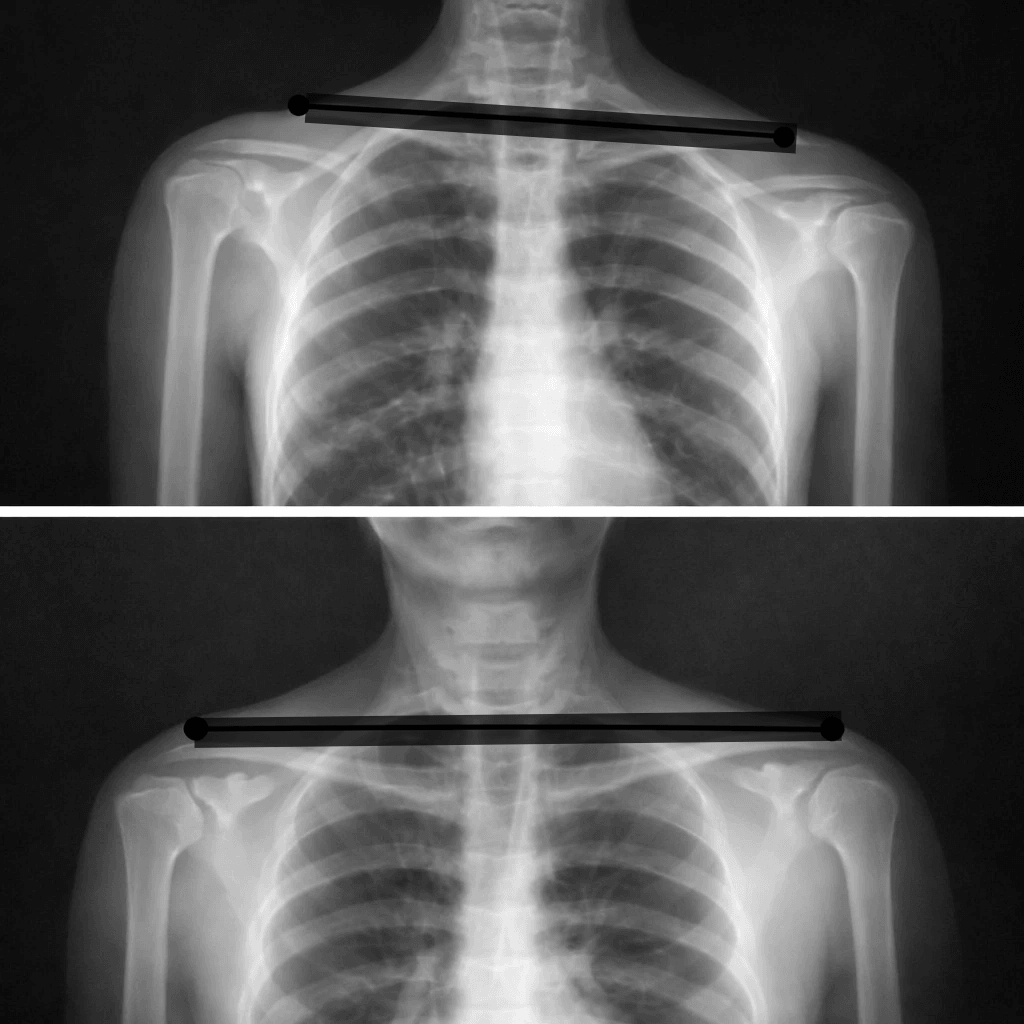

1. Two-scale test — our starting point

At the beginning, you will learn how to perform the two-scale test in order to objectively assess load asymmetry. Participants will stand on the scales themselves, and together we will analyze the results to understand what these differences mean.2. Posture correction and load equalization

The next step is to eliminate the detected asymmetries. We will continuously correct posture, restoring the proper loading pattern. Participants will see how improving balance affects body function and reduces tension.3. Techniques for dealing with different types of pain

A long-term patient, who competes in professional armwrestling, is preparing for the upcoming European Championships in Romania in just over a week. During a recent assessment using the bilateral weight distribution (two-scale test) which serves as my standard initial evaluation—he presented, for the first time since I’ve been working with him, a significant asymmetry: a 30 kg discrepancy 😮😮😮between sides.

Following the application of just one manual therapy technique, the asymmetry was reduced by 20 kg, 🤷♂️🤷♂️🤷♂️resulting in a remaining imbalance of 10 kg. While improved, this was still clinically excessive. After a second technique, the difference unfortunately increased to 15 kg—still an improvement compared to the original 30 kg. However, it wasn’t until the third intervention that complete symmetry was achieved.😀👌👌👌💪💪

This case illustrates the critical importance of assessing and restoring proper force distribution and postural balance in athletes. The two-scale test is a simple yet powerful diagnostic tool to detect and monitor such imbalances throughout the course of therapy.

In one study, the cause of vertebral fixation in over 80% of 105 patients was uneven weight bearing between the lower limbs exceeding 5 kg. After manipulation of fixed vertebrae, more than 70% of them were able to distribute weight equally while standing on two scales. Recurrence of the results after this treatment was found in 85% of patients. Better outcomes were observed when the fixed vertebrae were located in the upper cervical spine. If, during the two-scale standing test, a large difference in weight distribution between legs is detected, the craniocervical junction should be examined, including C2–C3. A difference of less than 2 kg does not seem significant.

According to Karl Lewit, a weight-bearing difference greater than 5 kg in adults and 3 kg in children should be considered pathological. However, based on my many years of clinical experience, I have concluded that even a difference exceeding 2 kg is already too large. With appropriate therapy, we are able to reduce this asymmetry to a minimum—around 2 kg, rather than 5 kg as Lewit originally suggested.

Sometimes deviations are not constant—in that case, we take average values. If the large difference is still noticeable, it should be considered significant and reassessed after treatment. It should also be verified whether the result is influenced by artefacts caused by pain in one leg.